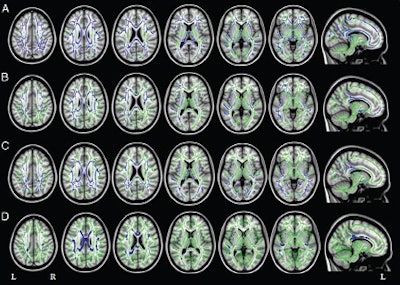

Filippi and colleagues used DTI to assess white-matter tracts in 28 patients with early-onset Alzheimer's, 12 with primary progressive aphasia, and 13 with posterior cortical atrophy. The 53 patients were matched in terms of age and gender with healthy control subjects for comparison purposes.

All three groups of Alzheimer's patients showed a common pattern of white-matter damage in the corpus callosum, fornix, and main anterior-posterior pathways, as well as cortical atrophy of the left temporoparietal regions and precuneus, the researchers found.

In the two atypical Alzheimer's groups in particular, white-matter damage was worse and more widely spread than expected based on cortical atrophy. Filippi and colleagues suggested that the damage may spread through white-matter tracts from atrophied regions to previously unaffected cortical areas.

In the patients with primary progressive aphasia, fractional anisotropy decreased in certain regions of the brain's left hemisphere, as well as in a small area of the frontal white matter in the right hemisphere. Patients with posterior cortical atrophy showed a symmetrical pattern of fractional anisotropy decrease, as well as diffusivity increases in several brain regions.